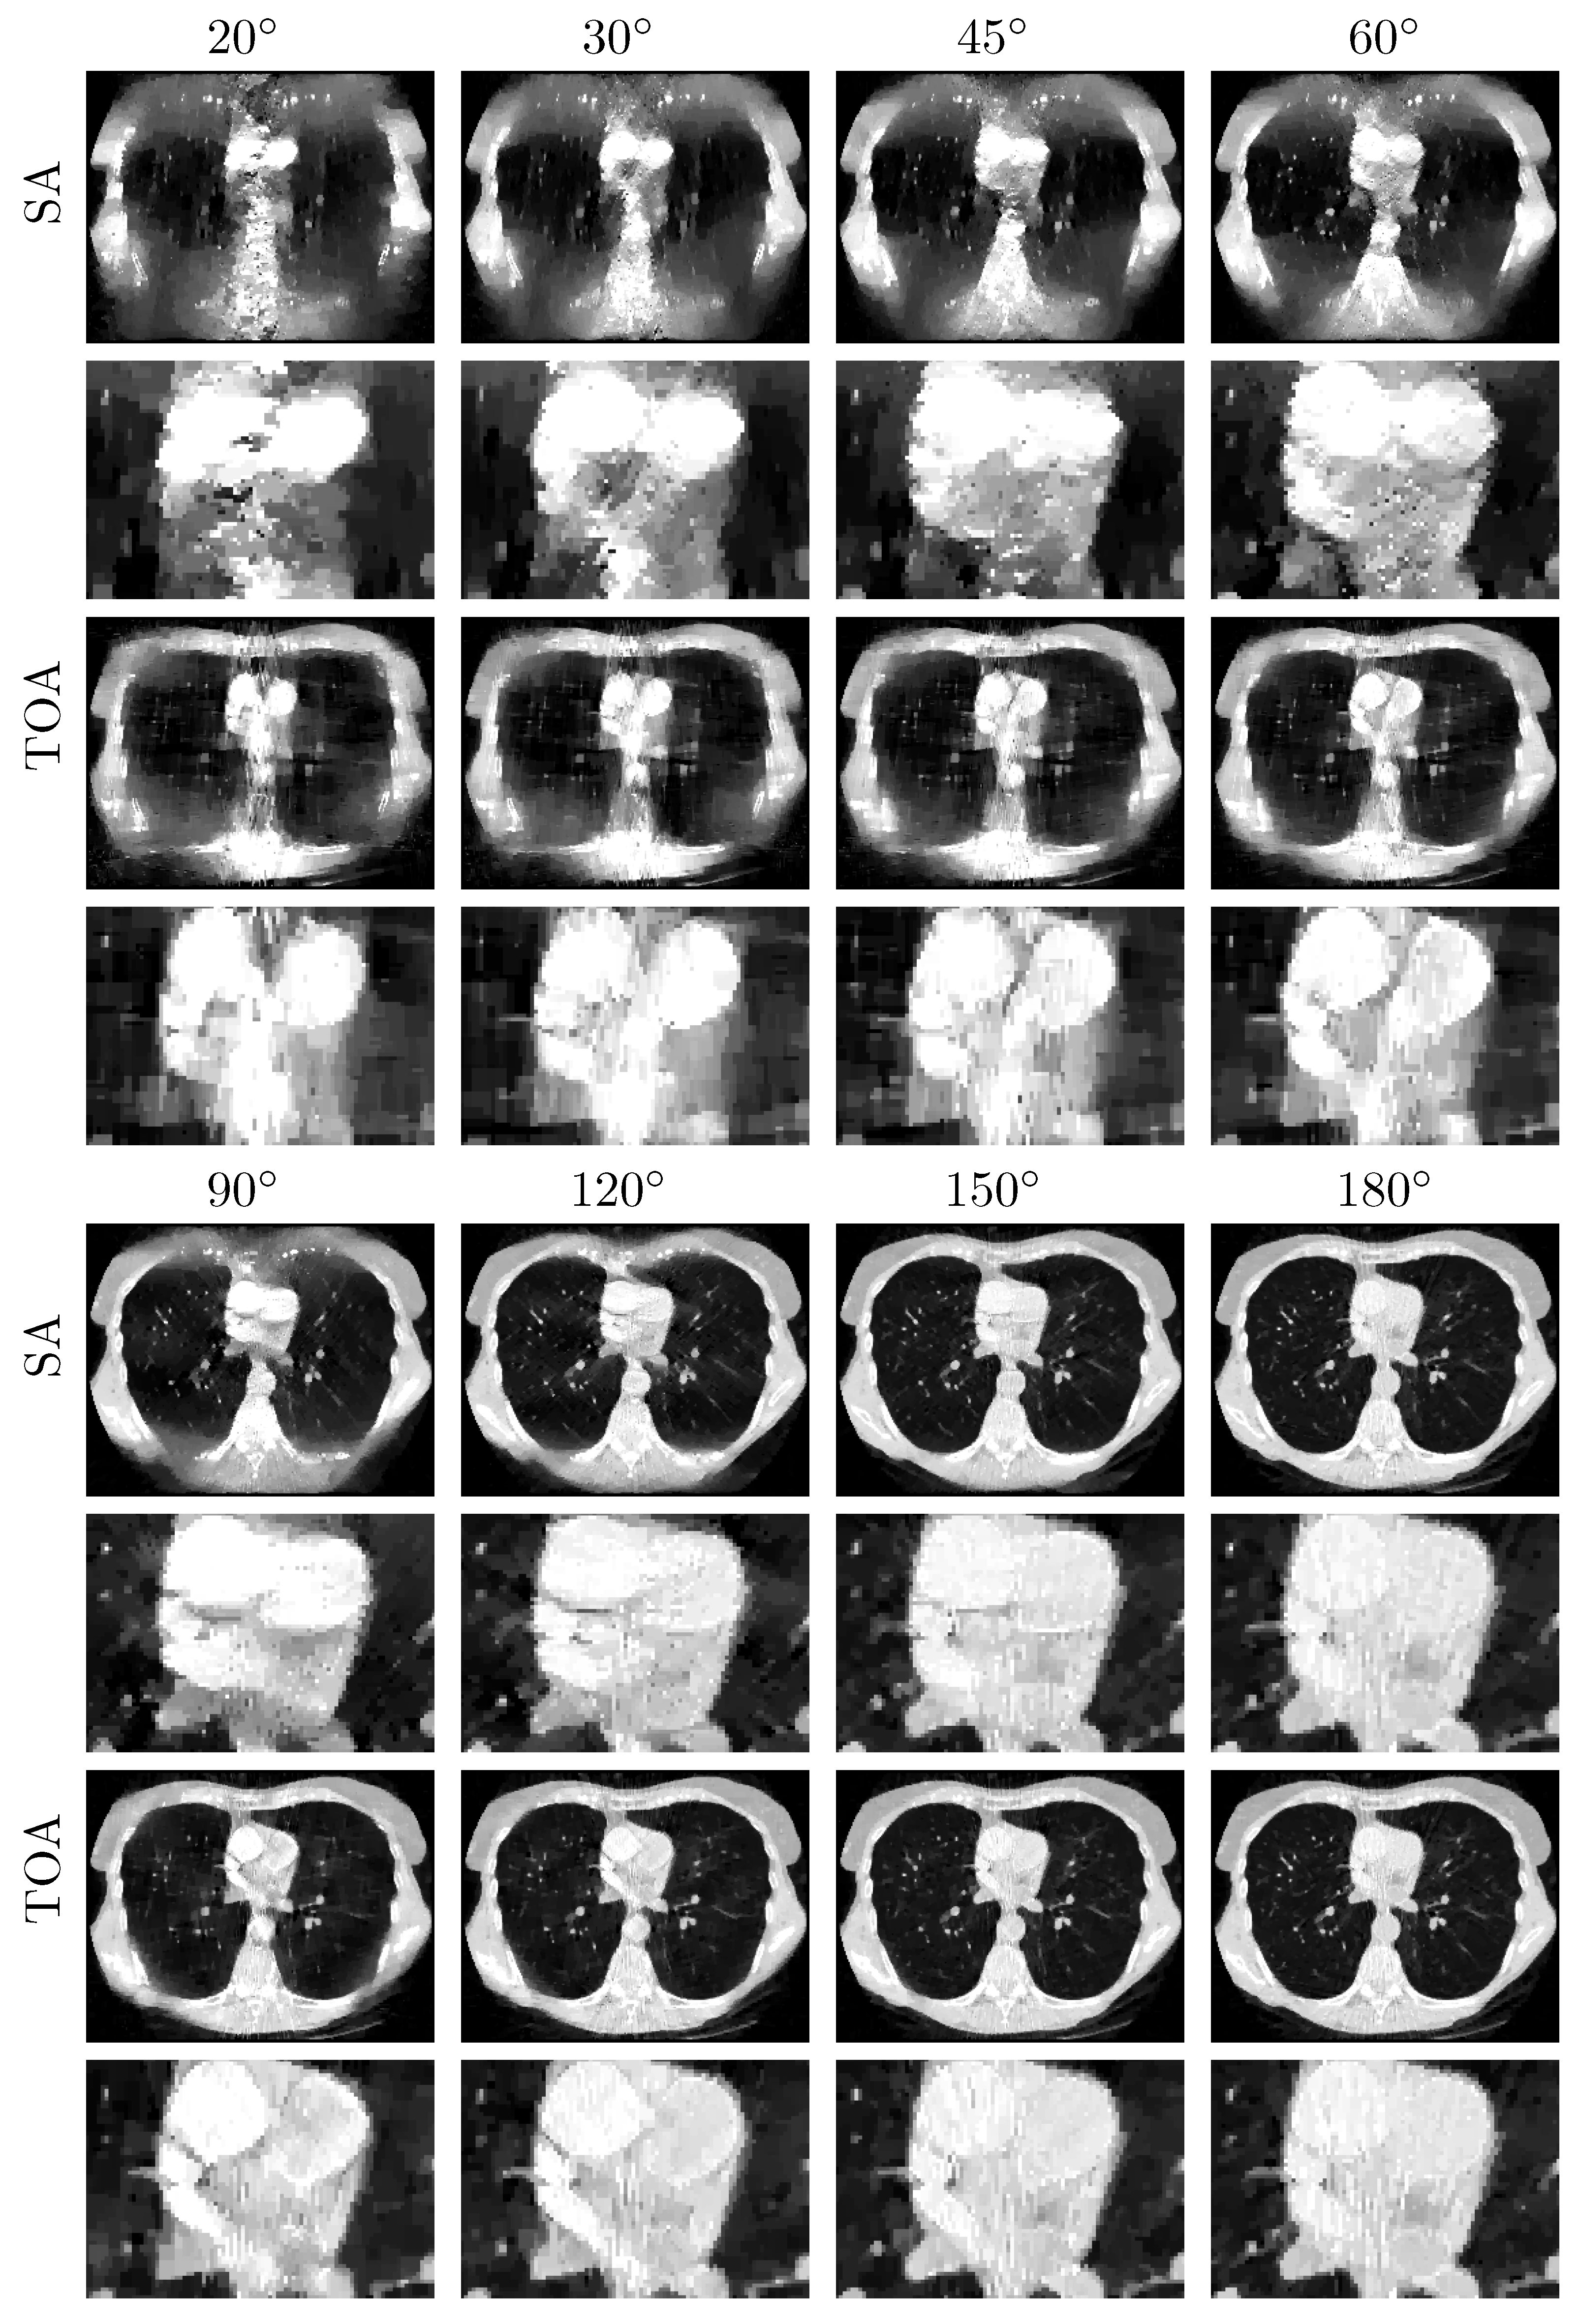

3.2.2. Image Reconstruction from Noiseless Data Acquired with SA and TOA Scans of LARs

3.2.3. Image Reconstruction from Noisy Data Acquired with SA and TOA Scans of LARs

3.3.1. Image Reconstruction from Noiseless Data Acquired with SA and TOA Scans of LARs

3.3.2. Image Reconstruction from Noisy Data Acquired with SA and TOA Scans of LARs